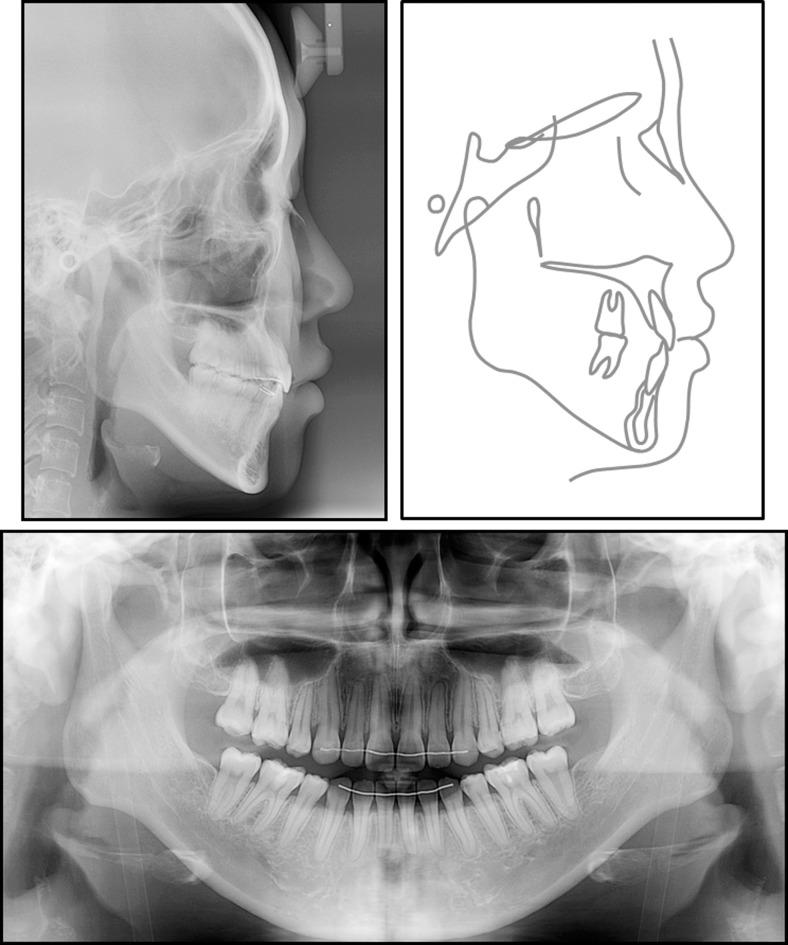

The posttreatment records show that the treatment objectives were achieved successfully. The facial profile was improved. Lip competence and an esthetic smile were observed (Figure 5). The posttreatment panoramic radiograph showed complete space closure and acceptable root parallelism in both arches with no significant root resorption (Figure 6). The posttreatment lateral cephalometric analysis and superimposition showed that the maxillary anterior and posterior teeth were intruded by 2.8 mm and 1.9 mm, respectively (Figure 7). In the mandible, the anterior and posterior teeth were intruded by 4.2 mm and 1.4 mm, respectively. The maxillary and mandibular incisors were retracted using maximum anchorage. As a result of the intrusion of all teeth in both arches, the mandible rotated counterclockwise (2.1°) and pogonion came forward by 3.0 mm.

Figure 6.

Posttreatment records: lateral cephalogram, cephalometric tracing, and panoramic radiograph.